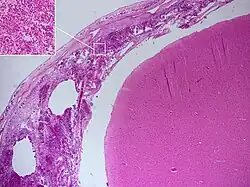

Histopathology of bacterial meningitis: autopsy case of a person with pneumococcal meningitis showing inflammatory infiltrates of the pia mater consisting of neutrophil granulocytes (inset, higher magnification).

Meningitis can be diagnosed after death has occurred. The findings from a post mortem are usually a widespread inflammation of the pia mater and arachnoid layers of the meninges. Neutrophil granulocytes tend to have migrated to the cerebrospinal fluid and the base of the brain, along with cranial nerves and the spinal cord, may be surrounded with pus – as may the meningeal vessels.[57]